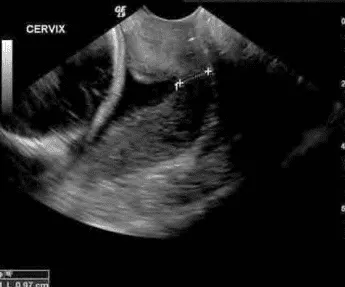

Chiều dài cổ tử cung

Đo siêu âm ngả âm đạo, từ lỗ ngoài đến lỗ trong cổ tử cung:

- Tuần 19-23 tuần 6 ngày: Nên khảo sát định kỳ.

- Tuần 24, nếu không triệu chứng mà cổ tử cung < 25 mm → nguy cơ sinh non tăng.

- Cơn gò xuất hiện mà cổ còn dài > 30 mm → nguy cơ sinh non trong 7 ngày chỉ 1%.

Hình dạng lỗ tử cung

Phần tiêu đề “Hình dạng lỗ tử cung”

- Cổ tử cung dạng U, Y: Nguy cơ cao.

- Dạng I (hình phễu nhẹ): Tiên lượng tốt hơn.